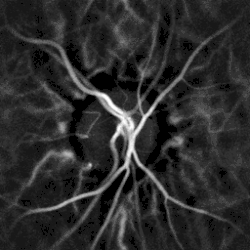

Remote, indirect monitoring of blood flow by laser Doppler

Laser Doppler imaging reveals retinal blood flow

Noninvasive hemodynamic monitoring of eye fundus vessels can be performed by Laser Doppler holography, with near infrared light. The eye offers a unique opportunity for the non-invasive exploration of cardiovascular diseases. Laser Doppler imaging by digital holography can measure blood flow in the retina and choroid, whose Doppler responses exhibit a pulse-shaped profile with time[38][39] This technique enables non invasive functional microangiography by high-contrast measurement of Doppler responses from endoluminal blood flow profiles in vessels in the posterior segment of the eye. Differences in blood pressure drive the flow of blood throughout the circulation. The rate of mean blood flow depends on both blood pressure and the hemodynamic resistance to flow presented by the blood vessels.